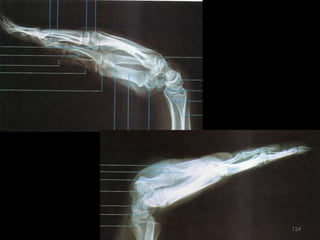

Incidência lateral cotovelo (látero-medial)65

66

67